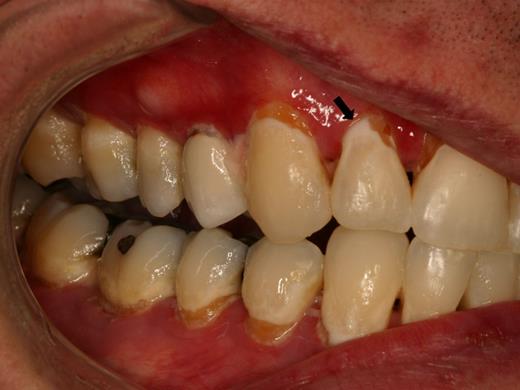

Rampant cervical dental caries affecting all of the teeth in a patient with cGVHD of the salivary glands. Demineralization changes (arrow) appear chalky white.